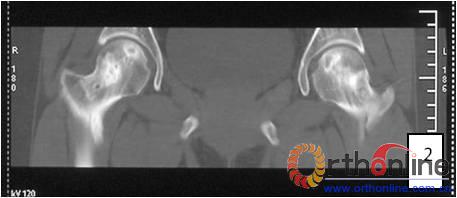

2.2 影像学结果 影像学结果与临床结果基本同步。临床结果优的36髋,34髋维持圆形且修复较完全(图1)。1例双髋Ⅲa激素性(SARS患者)ONFH,术后随访7年8月,X线片显示股骨头虽不圆,但临床HHS评分90分为优(图2)。功能为良的12髋,7髋股骨头不圆,但股骨头与髋臼匹配好,其余5髋股骨头维持圆形。临床评定为差的17髋,股骨头均有超过4mm塌陷,股骨头与髋臼匹配不好,股骨头内无折断,MRI未显示骨髓水肿,关节间隙呈不对称改变,CT扫描示软骨下骨折,MRI显示骨髓水肿。

图1 女,22岁,(1)双侧股骨头坏死右侧B型,左侧C1型;(2)打压植骨术(加入BMP2)后5年,CT显示植骨生长良好,关节功能正常(Harris评分96分);(3)术后7年关节功能维持正常,股骨头维持正常外形